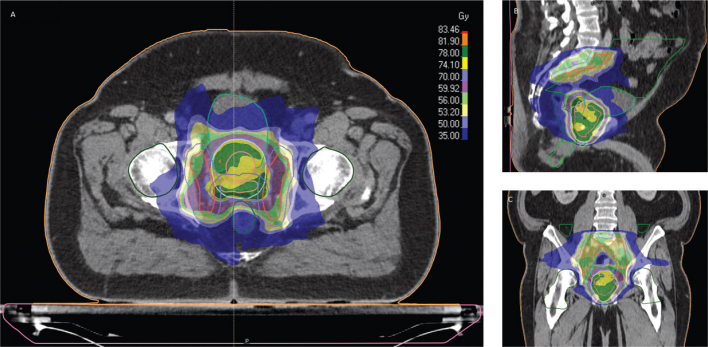

Material and methods: This prospective study includes 248 prostate cancer patients who received EBRT between 2017-2022. EBRT consisted of 56 Gy/39 fractions to the prostate, elective lymph nodes, and seminal vesicles with an integrated boost of 78 Gy to the prostate alone (≤T3a) or to the prostate and seminal vesicles (T3b). Rectal dose constraints were V50 Gy ≤50%, V70 Gy ≤20%, and V74 Gy ≤12%. Rectal bleeding was recorded at baseline and regularly duringfollow-up and included staff reported morbidity and patient reported outcome measures. Risk factors were evaluated in multivariate cox regression analysis.